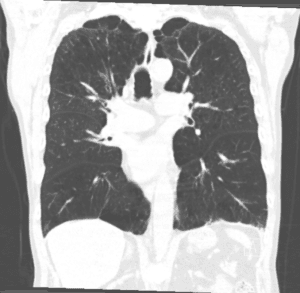

There has also been significant interest in applying ML algorithms to lung ultrasound. Lung ultrasound has gained increased use in the POC setting due to the wide number of clinically useful assessments it provides [21]. The quantitative assessment of B-line score (BLS) has become an important tool for assessing pulmonary congestion using POCUS [22]. B-lines are hyperechoic reverberation artifacts arising from the pleural surface that extend to the bottom of the screen without fading and move in tandem with lung sliding. Total BLS can be used to determine fluid overload (FO) severity score and a number of studies have demonstrated that BLS accurately quantifies pulmonary congestion outperforming the physical exam and chest x-ray [23–25]. Additionally, in the point of care setting, rapid assessment of a patient’s volume status can be a crucial tool in guiding clinical interventions. Yet, widespread use of this technique is limited partly due to the tedious nature of the assessment.

A number of groups, including our own, have developed DL models using CNN to automatically quantify B-line scores from POC lung ultrasound video clips. Recently, B. Christiana et al. developed a supervised CNN trained on 400 lung ultrasound clips to calculate total BLS in emergency department patients. They achieved a binary classification (B-lines present versus absent) sensitivity and specificity of 93% and 96% compared to an expert interpreter. In multiclass classification of B-line severity their DL model achieved a linear weighted kappa of 0.65 vs an interrater reliability of 0.87 [26]. Our own group has developed a DL model that uses a transformer block architecture CNN trained on 91 hemodialysis patients with ESRD to calculate total BLS and severity level. In preliminary results, our DL model demonstrated a binary classification (presence versus absence of B-lines) accuracy of 87.3% and a total BLS classification (scored 0-4) accuracy of 60.5% [27].

Point of care lung ultrasound has also shown great promise in the accurate diagnosing of community acquired pneumonia (CAP). It has demonstrated excellent diagnostic capabilities when performed by a trained sonographer compared to both clinical assessment and chest X-ray, while also avoiding unnecessary radiation exposure in vulnerable patients such as pediatric populations [28–30]. However, lung ultrasound is not included in the diagnostic workup for CAP partly because of inter-operator variability of lung ultrasound and training. DL approaches aimed at reducing these barriers are another emerging trend. In 2018, Correa et al. developed a neural network trained on 1450 CAP-positive ultrasound frames from a hospitalized pediatric population in Peru. The algorithm was successful in correctly identifying pneumonia infiltrates with 90.9% sensitivity and 100% specificity [31].

More recently, amidst the 2020 COVID-19 pandemic, there has been increased attention paid to increasing the diagnostic ability of clinicians to detect the presence of the novel coronavirus in patients. To this end, Born et al. developed a deep CNN trained on over 1100 COVID-19 confirmed lung ultrasound images to achieve a detection sensitivity of 0.96 and specificity of 0.79 and F1-score of 0.92 in a 5-fold cross validation [32]. The authors provide an open-access web service (POCOVIDScreen) that deploys the predictive model, allowing clinicians to both perform predictions on ultrasound lung images and upload their captured images to add to the database.